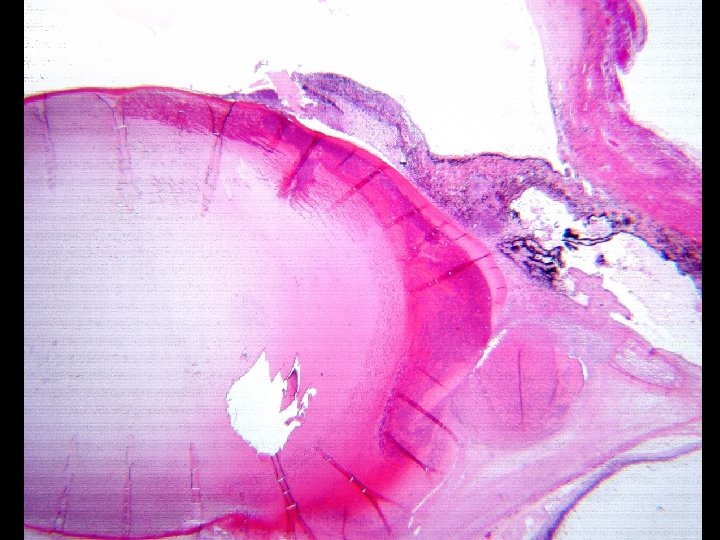

Canine Cases • 29 cases of 9, 300 ocular submissions • 10 documented cases of cat scratch • Typical ophthalmic findings included – chronic, poorly responsive anterior uveitis – cataract formation – +/- anterior or posterior synechiae, corneal scar, and/or glaucoma

What about phacoclastic inflammaton? Phacoclastic uveitis is a term used to characterize the inflammation seen around a ruptured lens as is seen in these cases. The term carries with it the implication that the inflammation is caused by the release of lens proteins otherwise sequestered. I believe that in these dogs the inflammation is do to bacterial infection and not simply exposure of lens proteins.